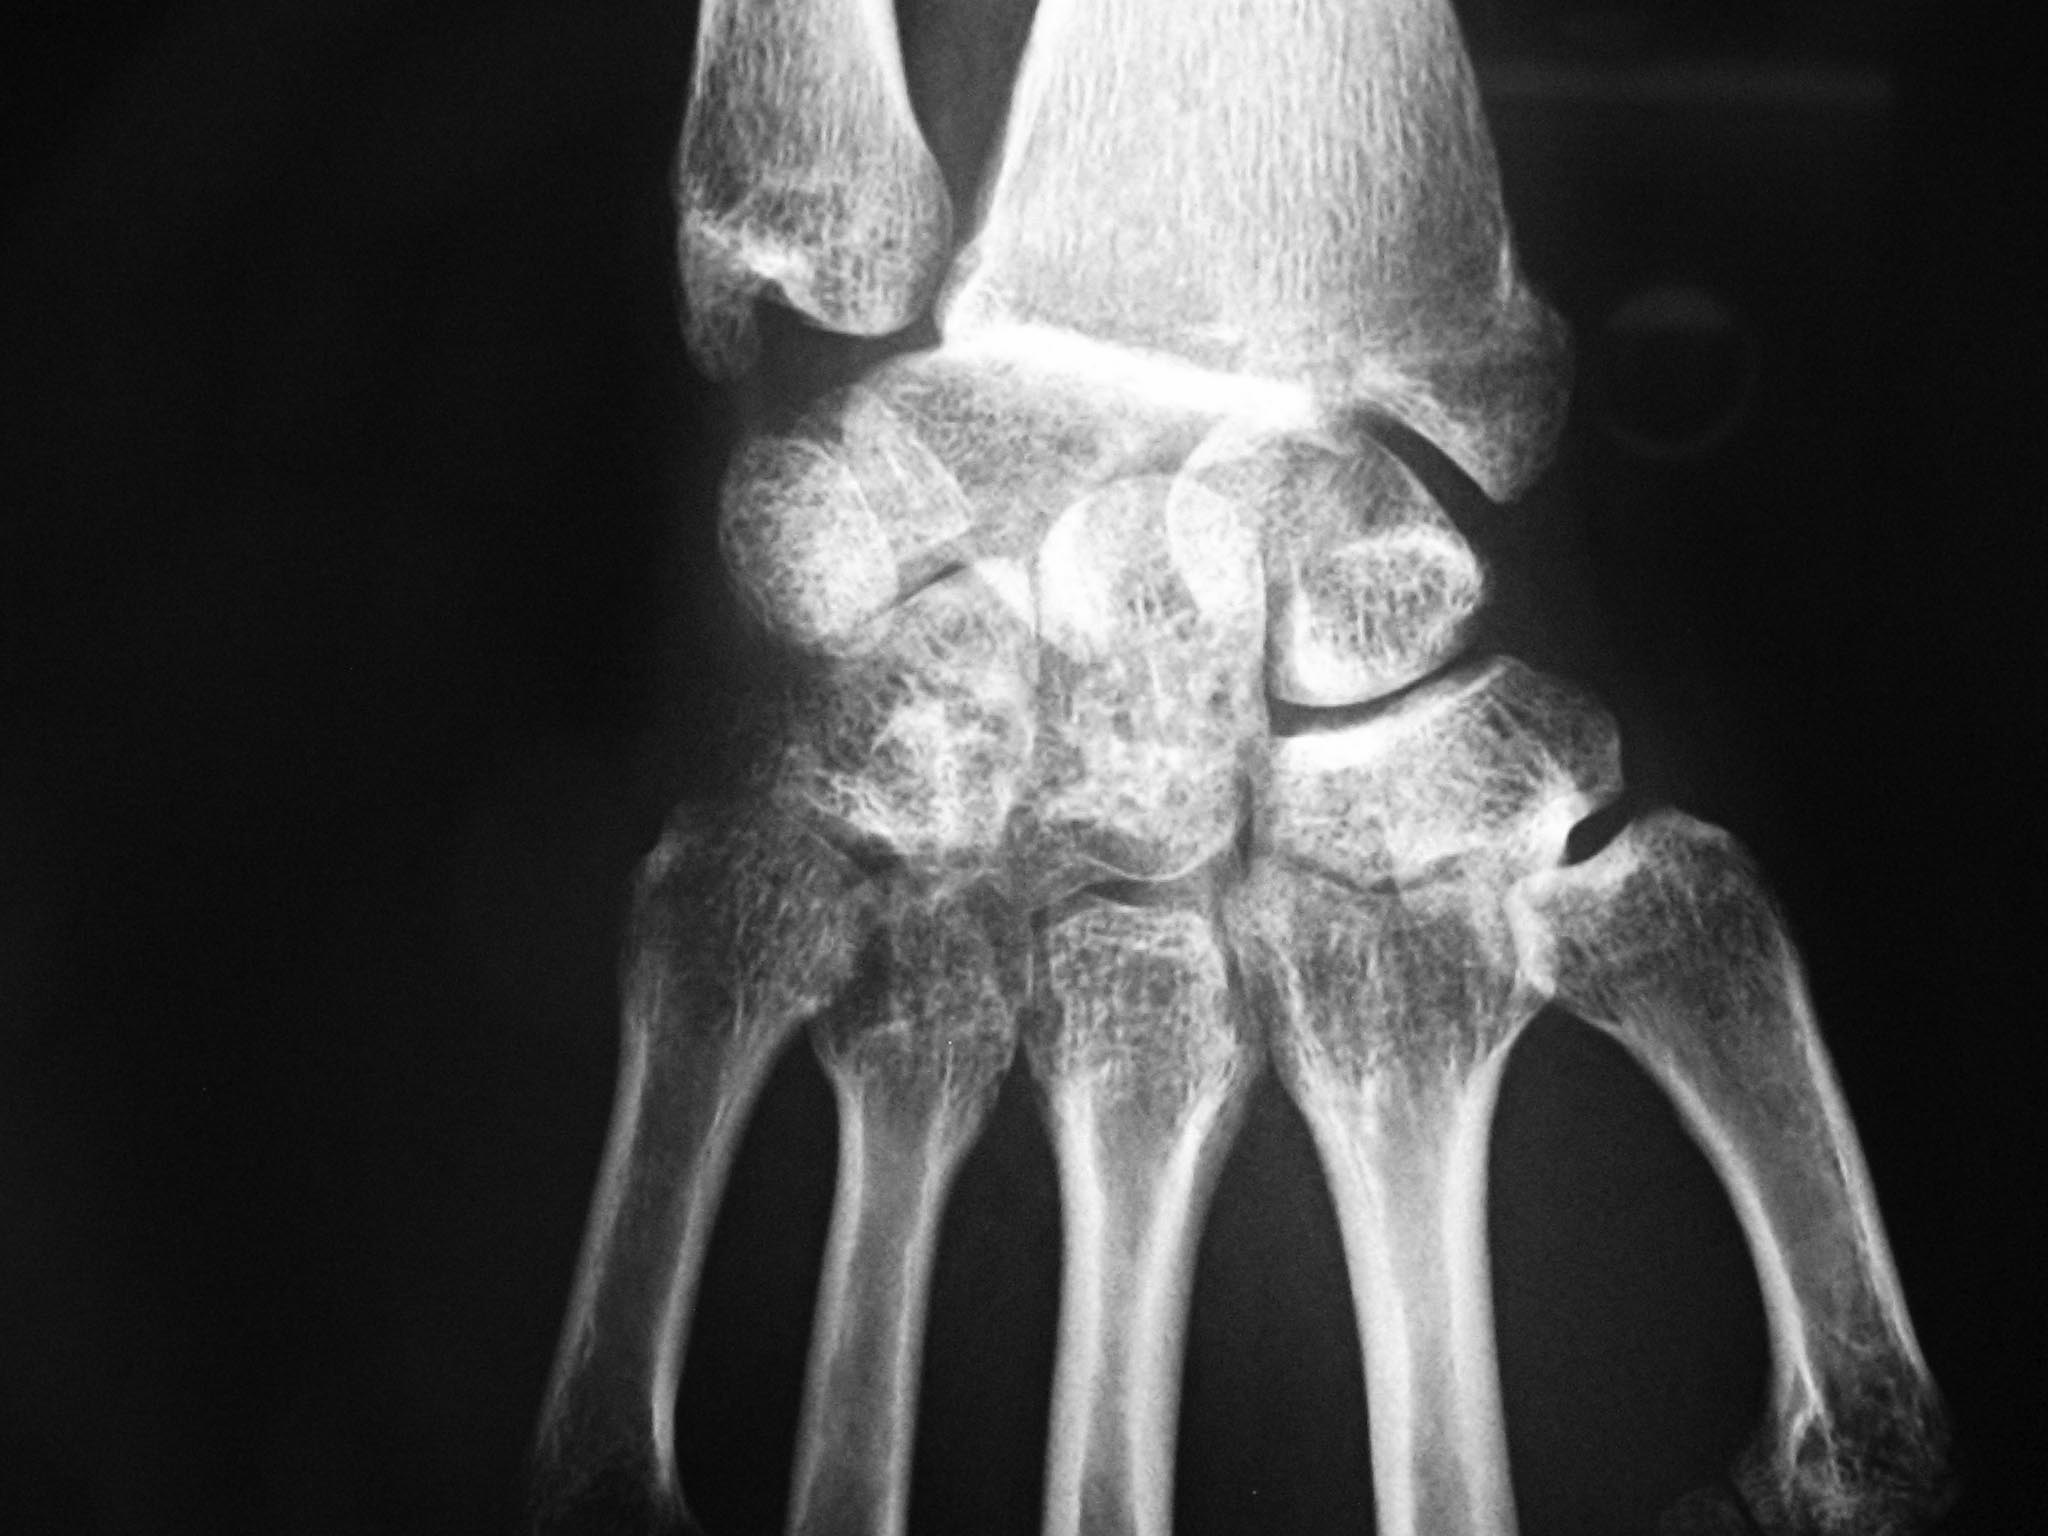

[Ortho] Травма кисти

прямая проекция